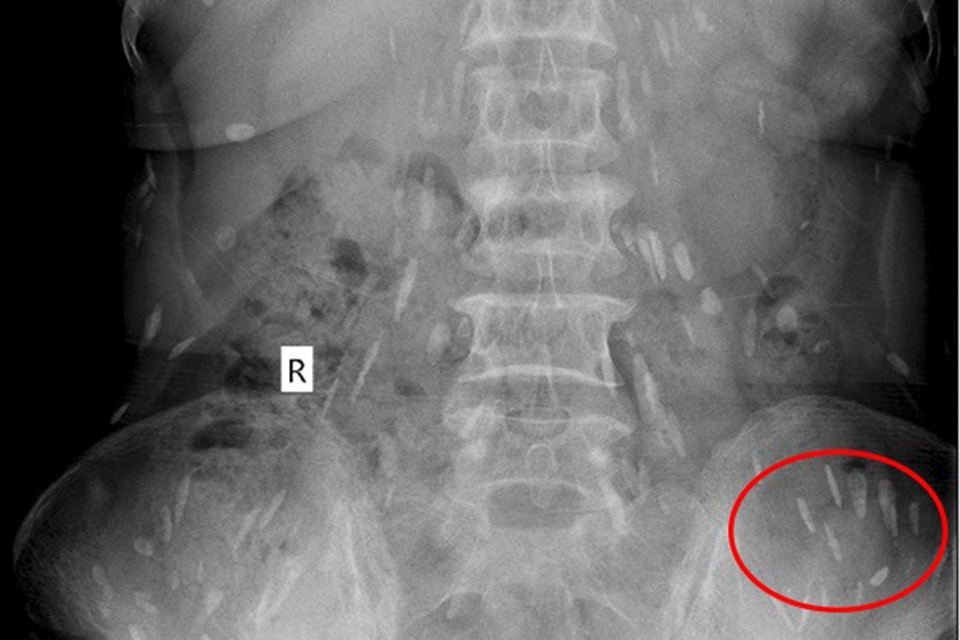

Rất nhiều sán lá gan (màu trắng) ký sinh trong cơ thể |

Qua thăm khám, các bác sĩ xác định bệnh nhân bị mắc bệnh sán lá gan sinh sống trong cơ thể nhiều năm, đang sinh sôi, lan ra trong nhiều bộ phận cơ thể.